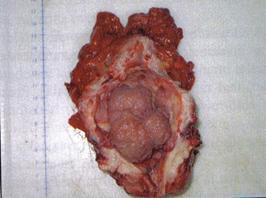

a

Fig.5 Piese de cistectomie: a)tumora solida, b) tumora vegetanta sesila; [51].

b